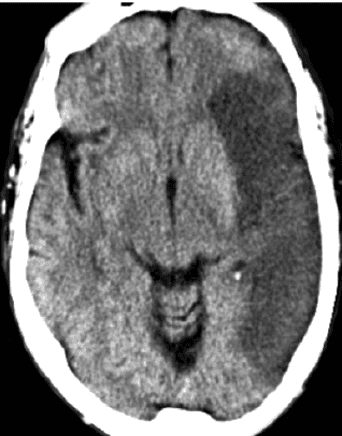

La expansión de la selección por imagen consolida un cambio de paradigma: ya no basta con detectar hipodensidad, oclusión o edema. Hoy se espera que la imagen distinga entre núcleo isquémico establecido, penumbra recuperable y escenarios en los que intervenir puede cambiar el pronóstico funcional del paciente.

El informe radiológico deja de ser una descripción retrospectiva del evento. Ahora define elegibilidad terapéutica, orienta trombólisis o trombectomía en ventanas extendidas, y exige lectura integrada de TAC simple, angioTAC, perfusión y, cuando corresponde, RM multiparamétrica. La interpretación ya no es solo diagnóstica: es estratégica.

En la práctica, esto exige una secuencia operativa clara: TAC sin contraste para descartar hemorragia y detectar signos tempranos, angioTAC para identificar oclusión de gran vaso y estudios de perfusión o RM para valorar tejido recuperable. La calidad del desenlace depende cada vez más de la calidad y velocidad de esa cadena.